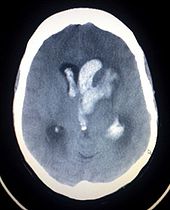

Intracranial hemorrhage is the accumulation of blood anywhere within the skull vault. A distinction is made between intra-axial hemorrhage (blood inside the brain) and extra-axial hemorrhage (blood inside the skull but outside the brain). Intra-axial hemorrhage is due to intraparenchymal hemorrhage or intraventricular hemorrhage (blood in the ventricular system). The main types of extra-axial hemorrhage are epidural hematoma (bleeding between the dura mater and the skull), subdural hematoma (in the subdural space) and subarachnoid hemorrhage (between the arachnoid mater and pia mater). Most of the hemorrhagic stroke syndromes have specific symptoms (e.g. headache, previous head injury).

Intracerebral hemorrhage (ICH) is bleeding directly into the brain tissue, forming a gradually enlarging hematoma (pooling of blood). It generally occurs in small arteries or arterioles and is commonly due to hypertension, trauma, bleeding disorders, amyloid angiopathy, illicit drug use (e.g. amphetamines or cocaine), and vascular malformations. The hematoma enlarges until pressure from surrounding tissue limits its growth, or until it decompresses by emptying into the ventricular system, CSF or the pial surface. A third of intracerebral bleed is into the brain's ventricles. ICH has a mortality rate of 44 percent after 30 days, higher than ischemic stroke or even the very deadly subarachnoid hemorrhage.

Stroke is diagnosed through several techniques: a neurological examination, CT scans (most often without contrast enhancements) or MRI scans, Doppler ultrasound, and arteriography. The diagnosis of stroke itself is clinical, with assistance from the imaging techniques. Imaging techniques also assist in determining the subtypes and cause of stroke. There is yet no commonly used blood test for the stroke diagnosis itself, though blood tests may be of help in finding out the likely cause of stroke.

- CT scans (without contrast enhancements)

- sensitivity= 89%

- specificity= 100%